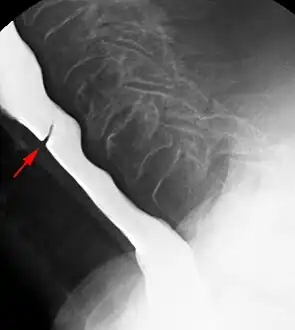

- Esophageal web stenosis in barium swallow examination lateral view.

- Web with "jet-phenomenon". Arrowhead on incomplete opening of the upper esophageal sphincter.